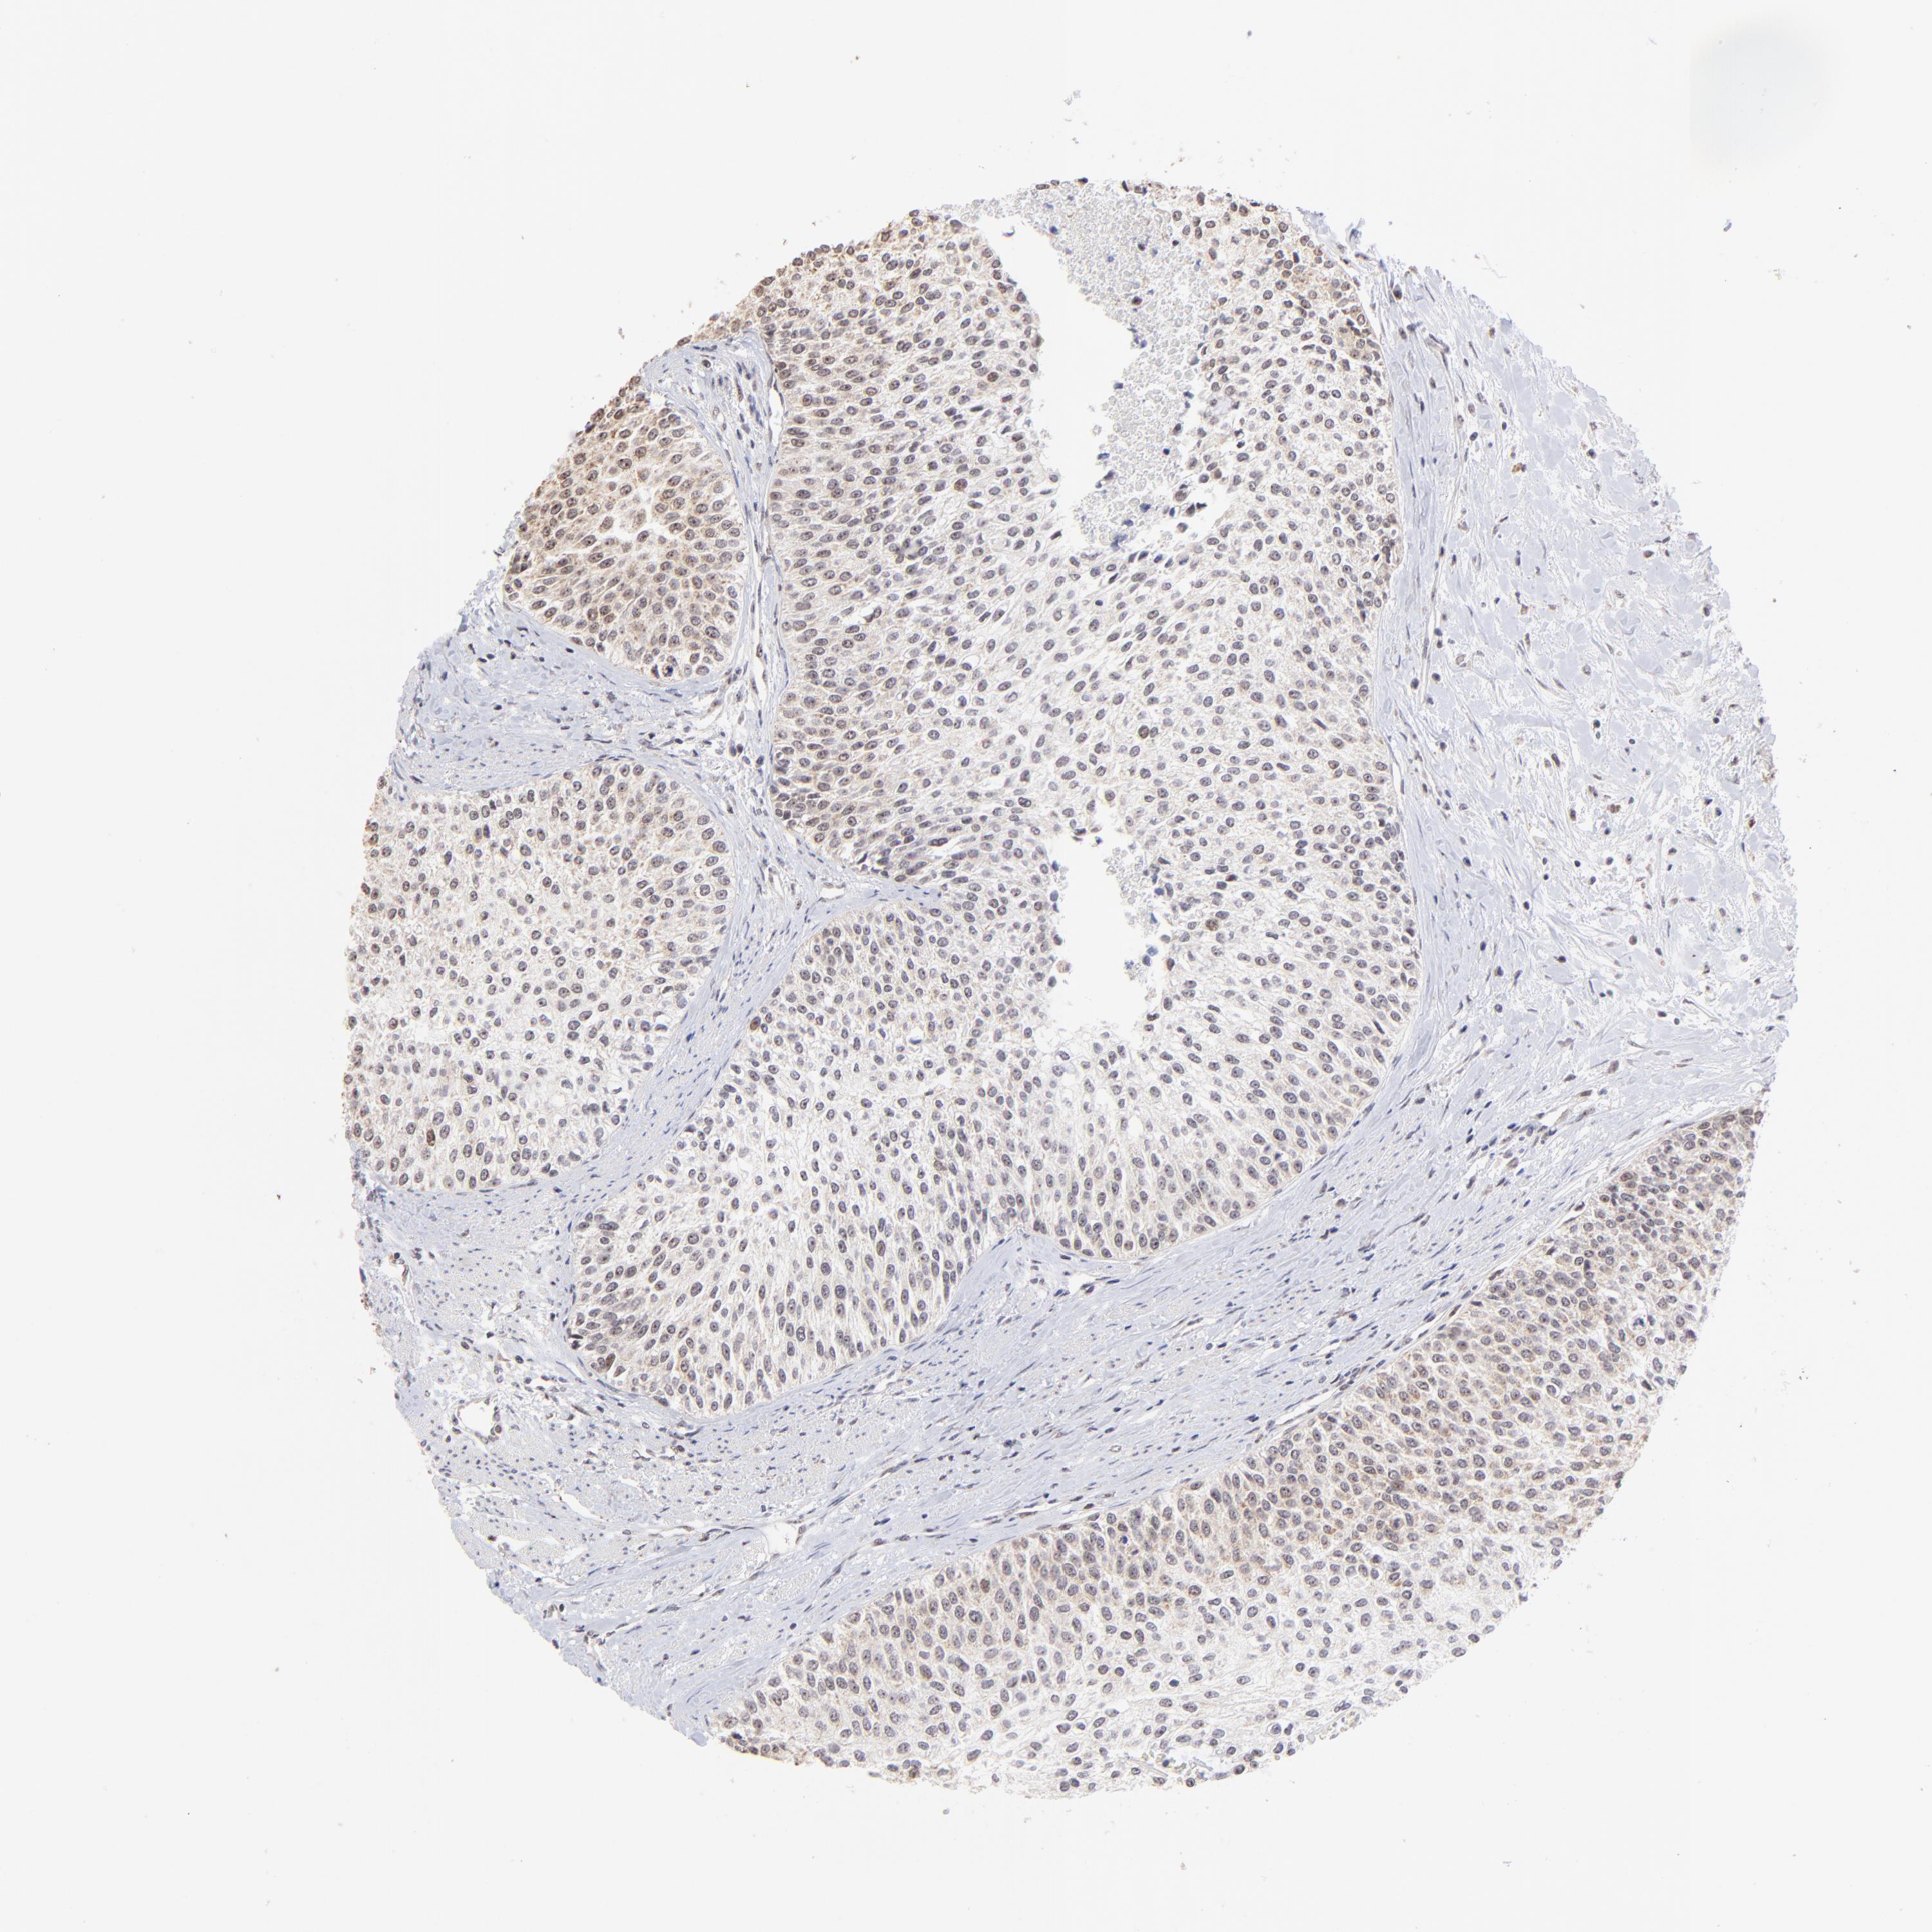

UROTHELIAL CANCER - Protein expressioni

A mouse-over function shows sample information and annotation data. Click on an image to view it in a full screen mode. Samples can be filtered based on level of antibody staining by selecting one or several of the following categories: high, medium, low and not detected. The assay and annotation is described here.

Antibody stainingi

Antibody staining in the annotated cell types in the current human tissue is reported as not detected, low, medium, or high, based on conventional immunohistochemistry profiling in selected tissues. This score is based on the combination of the staining intensity and fraction of stained cells.

Each image is clickable and will lead to virtual microscopy that enables deeper exploration of all samples and also displays staining intensity scores, fraction scores and subcellular localization as well as patient and tissue information for each sample.

Antibody HPA003142

Staining

High

Medium

Low

Not detected

Intensity

Strong

Moderate

Weak

Negative

Quantity

>75%

75%-25%

<25%

None

Location

Nuclear

Cytoplasmic/membranous

Cytoplasmic/membranous,nuclear

Urothelial carcinoma, High grade